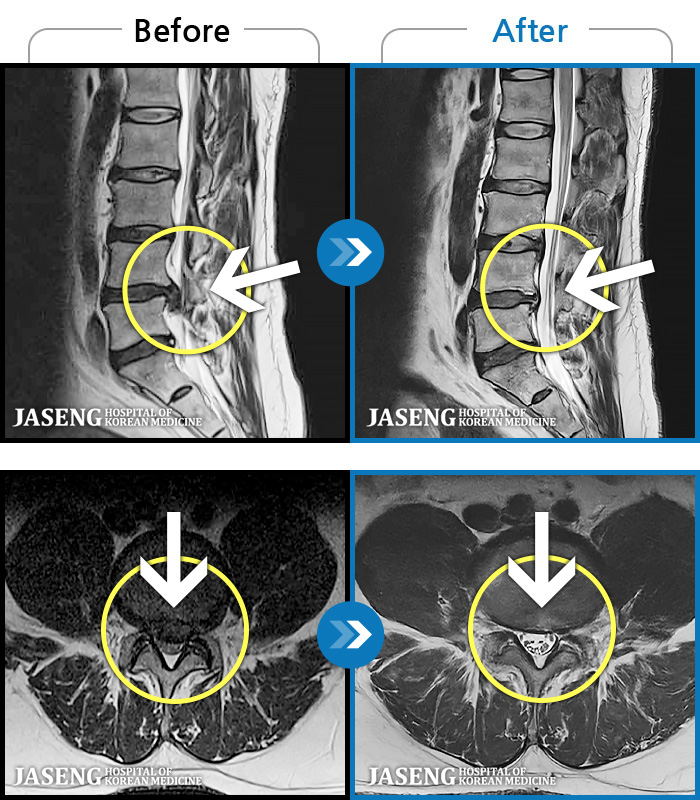

MRI ġ

1,237 MRI ũ ʸ Ȯϼ.

㸮 ϻ .